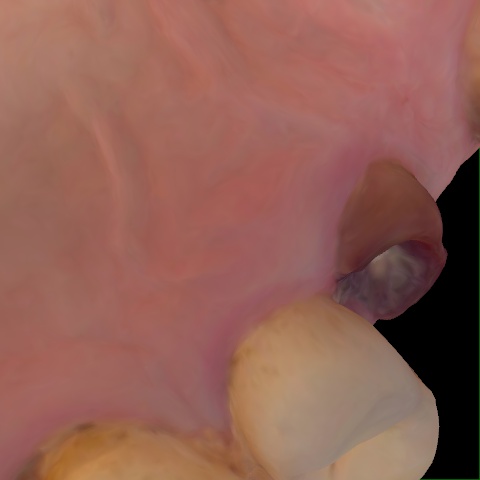

Annotated as "Good"

Original Image Rendering Image